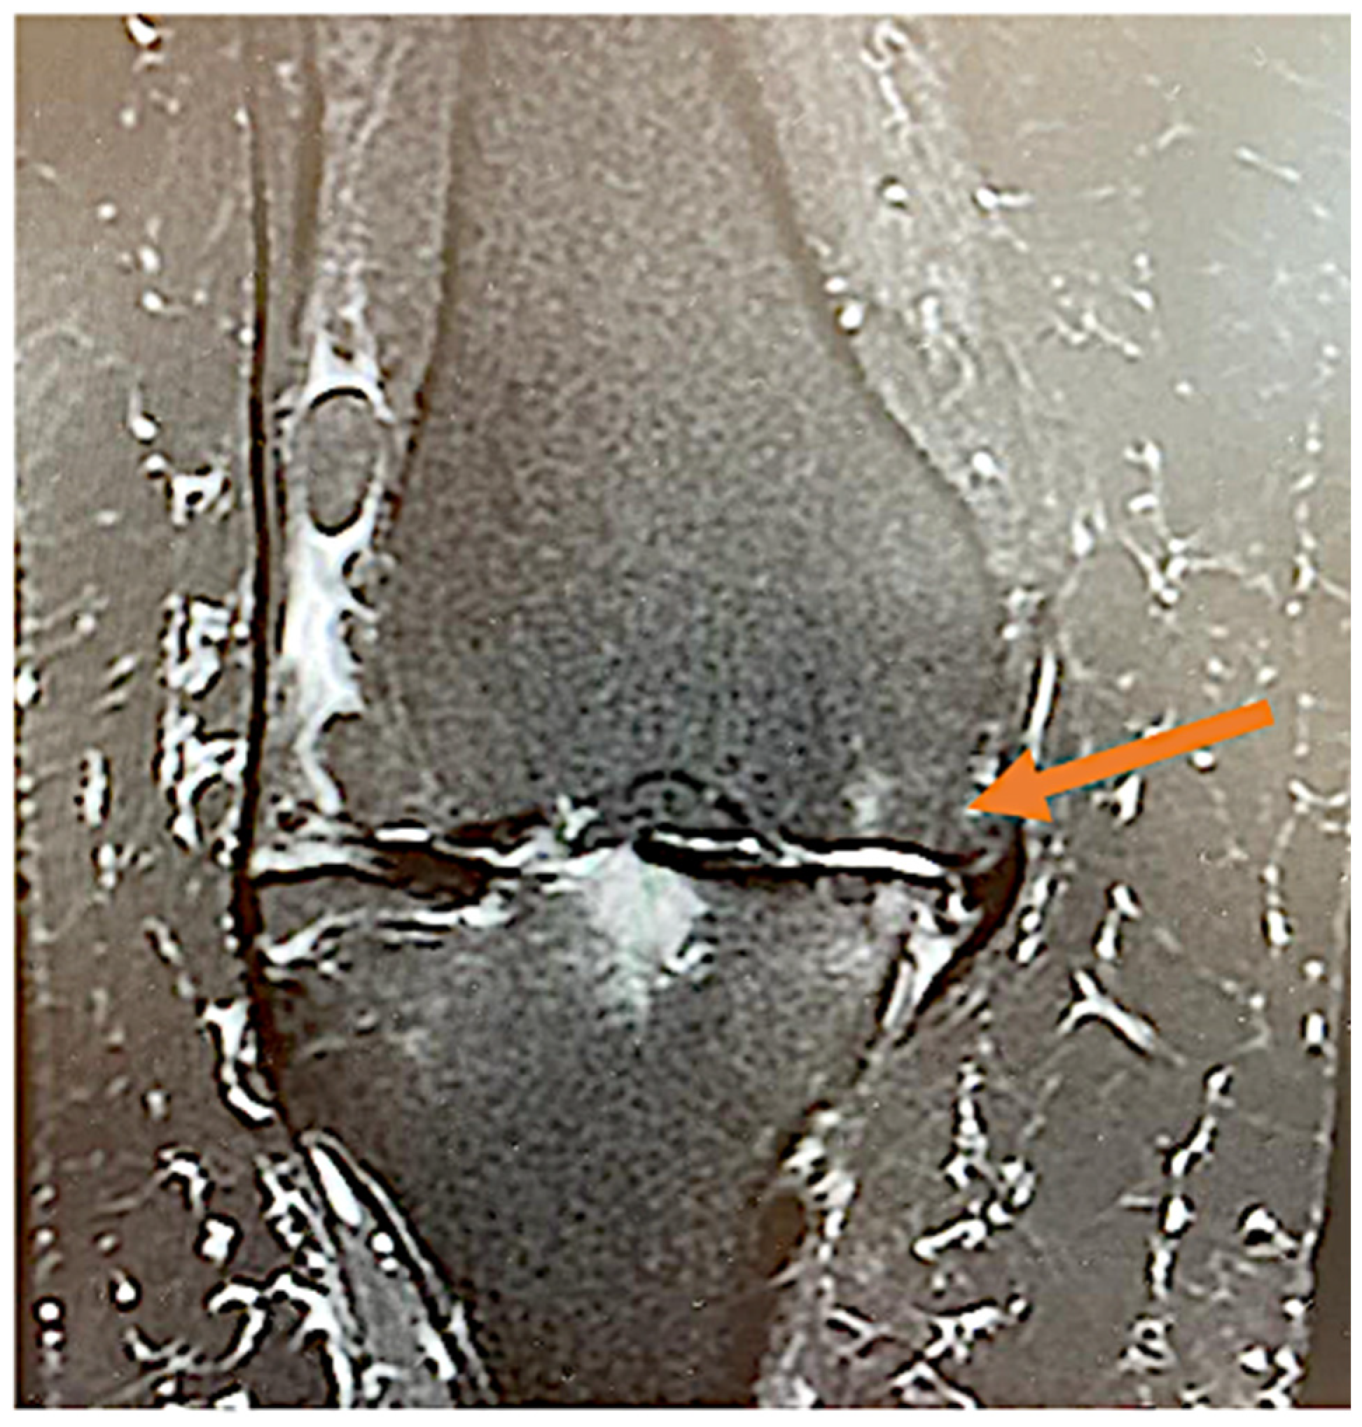

- Okuno, Y.; Korchi, A.M.; Shinjo, T.; Kato, S.; Kaneko, T. Midterm Clinical Outcomes and MR Imaging Changes after Transcatheter Arterial Embolization as a Treatment for Mild to Moderate Radiographic Knee Osteoarthritis Resistant to Conservative Treatment. J. Vasc. Interv. Radiol. 2017, 7, 995–1002. [Google Scholar] [CrossRef] [PubMed]